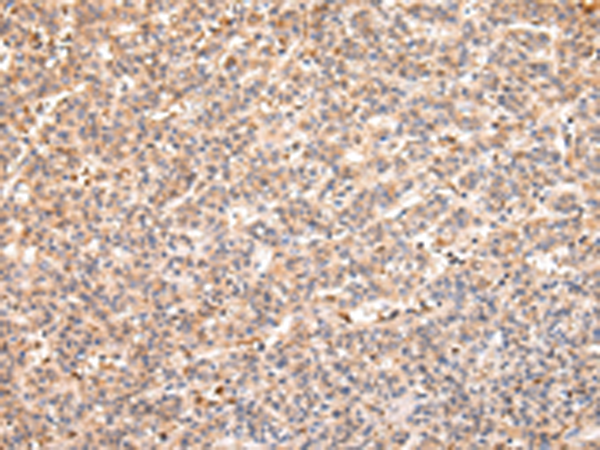

分类: 科研抗体货号: P11263别名: P2Y11应用: WB,IHC反应种属: Human